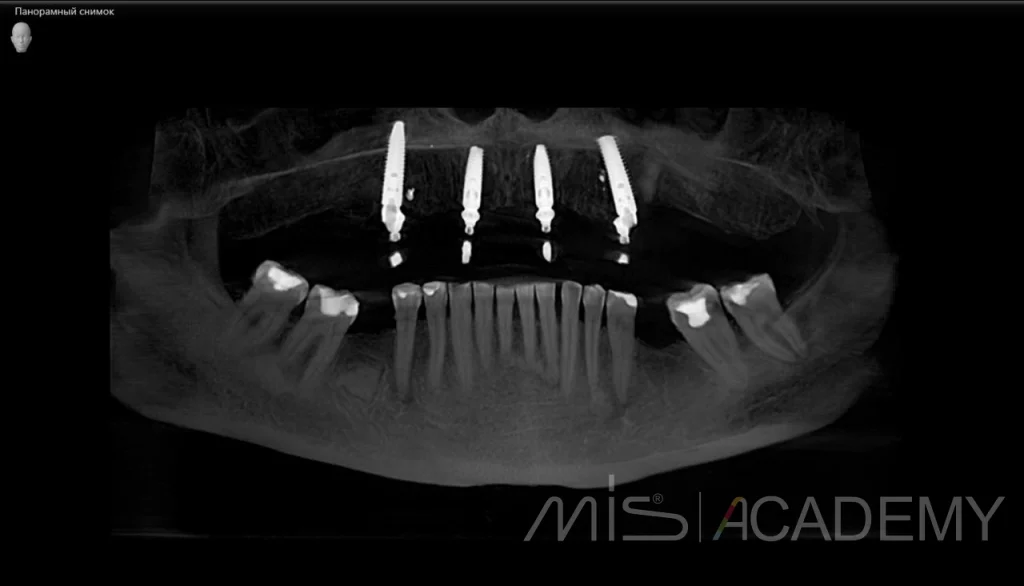

2. Установка 4 имплантов MIS C1 + Multiunit.

3. В области 1.4 проведен B2S.

4. В областях 1.4, 1.2, 1.1, 2.1, 2.2, 2.4 проведена подсадка мягких тканей с бугра.